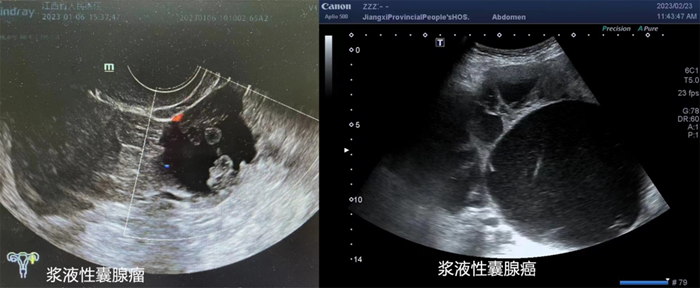

超声检查是卵巢囊肿最常用的检查方式,有性生活史者建议首选经阴道超声检查,无性生活或囊肿过大超出盆腔也可选择腹部超声检查。超声显示囊肿呈囊性无回声、囊壁薄、无实性成分、无分隔及血流信号者称为单纯囊肿。

超声显示囊肿内部有分隔伴异常回声称为单房性/多房性囊肿。

超声提示囊肿为囊实性或内壁有乳头样突起时,恶性风险增至10%。